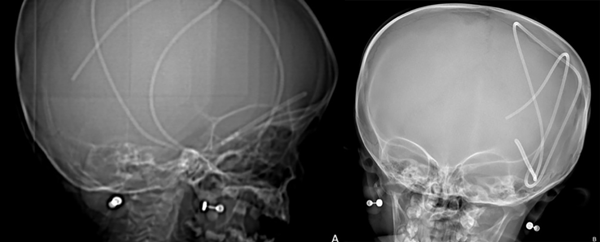

En las siguientes 2 semanas la paciente presentó cefalea de manera progresiva más deterioro del nivel de conciencia y vómitos, por lo que se indicó TC y radiografía de control, en estas se observó el catéter de derivación dentro del espacio subdural en su totalidad debido a migración cefálica completa (Figuras 1 a 3).

Figura 1. Radiografía de cráneo en vista lateral (A) y anteroposterior (B). Se observa el catéter de derivación subduroperitoneal en localización intracraneana completa luego de ocurrir la migración cefálica.